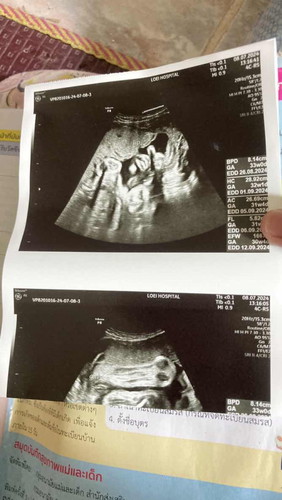

สวัสดีค่ะแม่ๆทุกคน วันนี้ก็ได้ไปอัลตร้าซาวด์และฟังเสียงหัวใจลูกเต้น ปรากฏว่าลูกแข็งแรงดีค่ะ กลับหัวแล้วด้วย สรุปก็ได้ลูกสาวสมใจค่ะ👧🏻❤️ ดิ้นและถีบเก่งมาก แม่ๆคลอดเดือนไหนกันบ้างคะ #ทีมกันยายน67

บ้านนี้กำหนดคลอด 14 กันยา อัลตร้าซาว 30 สัปดา 4 วัน น้องอยุ่ท่าหัวลงแล้วค่ะ